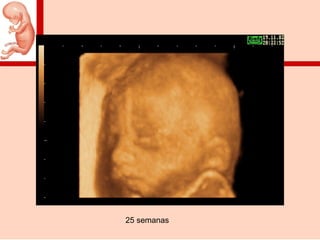

25 semanas